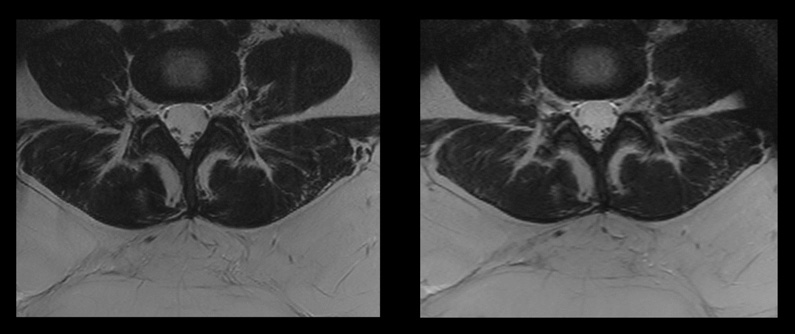

Compressed SENSEを使用すると、SARが低減されます。これは患者によい影響をもたらすとともに、より難しい検査を受け入れることができるようにもなります。

特殊なSARレベルが要求される金属製のインプラントを装着した患者に対しては、MRIスキャンが困難な場合があります。Compressed SENSEを併用するとMRI検査全体に要する時間を短縮でき、条件付きMR対応インプラントメーカーが指定した制限範囲内にSARを抑制できます。これにより、MRIスキャンに適さなかった患者の検査を行うことができます。また、撮像時間が短縮されるため、患者の快適性がより向上します。

Compressed SENSE使用時/不使用時の脊椎シーケンスの比較

左の画像:従来の撮像(SARレベル:2.5W/kg、スキャン時間:7分33秒)

右の画像:Compressed SENSEによる撮像(SARレベル:1.9W/kg、スキャン時間:3分21秒)